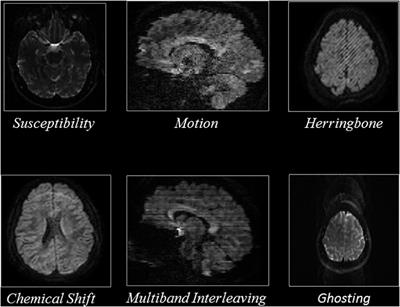

Automated Multiclass Artifact Detection in Diffusion MRI Volumes via 3D Residual Squeeze-and-Excitation Convolutional Neural Networks